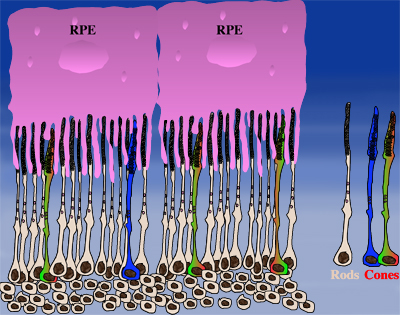

How could the observations of nutritionally deprived cones explain the dependence of cones on rods? Photoreceptor outer segments interact with the retinal-pigmented epithelium, which a single sheet of cells adjacent to the photoreceptor layer. The outer segments-retinal-pigmented epithelium interactions are vital since the retinal-pigmented epithelium provides nutrition and oxygen to PRs. Roughly 95% of all PRs in mouse and human are rods and approximately 20-30 outer segments contact one retinal-pigmented epithelium cell. Thus, only 1-2 of those retinal-pigmented epithelium-outer segment contacts are via cones. In Retinitis Pigmentosa rods die primarily due to a mutation in a rod specific gene. The loss of rods, which comprise ~95% of all photoreceptors leads to a collapse of the outer nuclear layer. During this collapse, the few remaining cone:retinal-pigmented epithelium interactions are likely perturbed (Rollover image below). If these interactions drop below a critical threshold required for the proper flow of nutrients, the loss of rods results in reduced flow of nutrients to cones. By cross-comparing 4 mouse models of Retinitis Pigmentosa we found in our studies that cone death starts always after ~90% of rods have died. This cell density thus represent the crucial threshold of remaining cells after which flow of nutrition is perturbed. This mechanism also explains why the loss of cones does not lead to rod death. Since in humans and mouse, cones are less than 5% of all PRs, the critical threshold that perturbs outer segment-retinal-pigmented epithelium interactions is not be reached. Additionally, it also explains why in cone rich species such as Zebrafish loss of cones does affect rod survival. In summary, the determining factor for the less abundant photoreceptor cell type to die when the more abundant one dies, is the local ratio between the 2 photoreceptor cell types.

| During rod cell death the cell density decreases in the outer nuclear layer (rollover first panel to see the number of rods decrease). The reduced number of rods in the outer nuclear layer results in a collapse of the ONL and put stress on the outer segment retinal-pigmented epithelium interactions (rollover second panel to detach the outer segments from the retinal-pigmented epithelium). At later stages of degeneration a retinal cross-section looks similar to what is seen in the last panel. Once this critical threshold of remaining cells is breached cones start to die due to reduced nutrient flow while the remaining rods die due to the intrinsic mutation. | ||